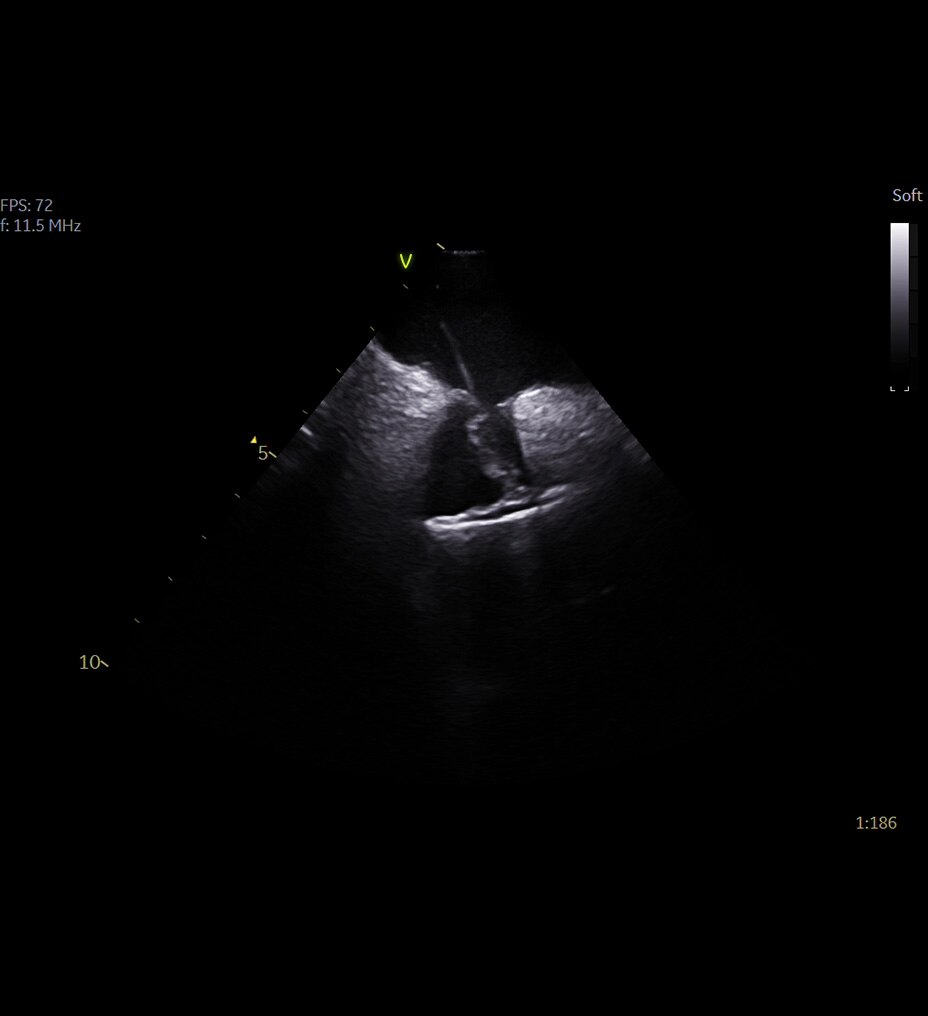

Revolution Ascend; rutin, kardiyak, büyük bedenli hasta, Acil Servis ve girişimsel dahil olmak üzere çoğu ortama yönelik özelliklere sahiptir.

BT deneyiminin en çok zaman alan kısmı taramanın kendisi değil; hastayı hazırlama, rekonstrüksiyon ve raporlama süresi gibi taramanın dışında kalan adımlardır. BT deneyimindeki tüm tarama öncesi ve tarama sonrası adımları analiz ettik ve önemli bulgularımızı Revolution Ascend'in tasarımına dahil ettik. Bu tasarımının sonucunda Revolution Ascend, yüksek BMI değerine sahip hastaları ve girişimsel prosedürleri verimli bir şekilde yönetebilme gibi yaygın endişeleri ortadan kaldırır. Ayrıca, tüm görüntüleme modları için kullanımı kolay iki düğmeli tarama sağlar.